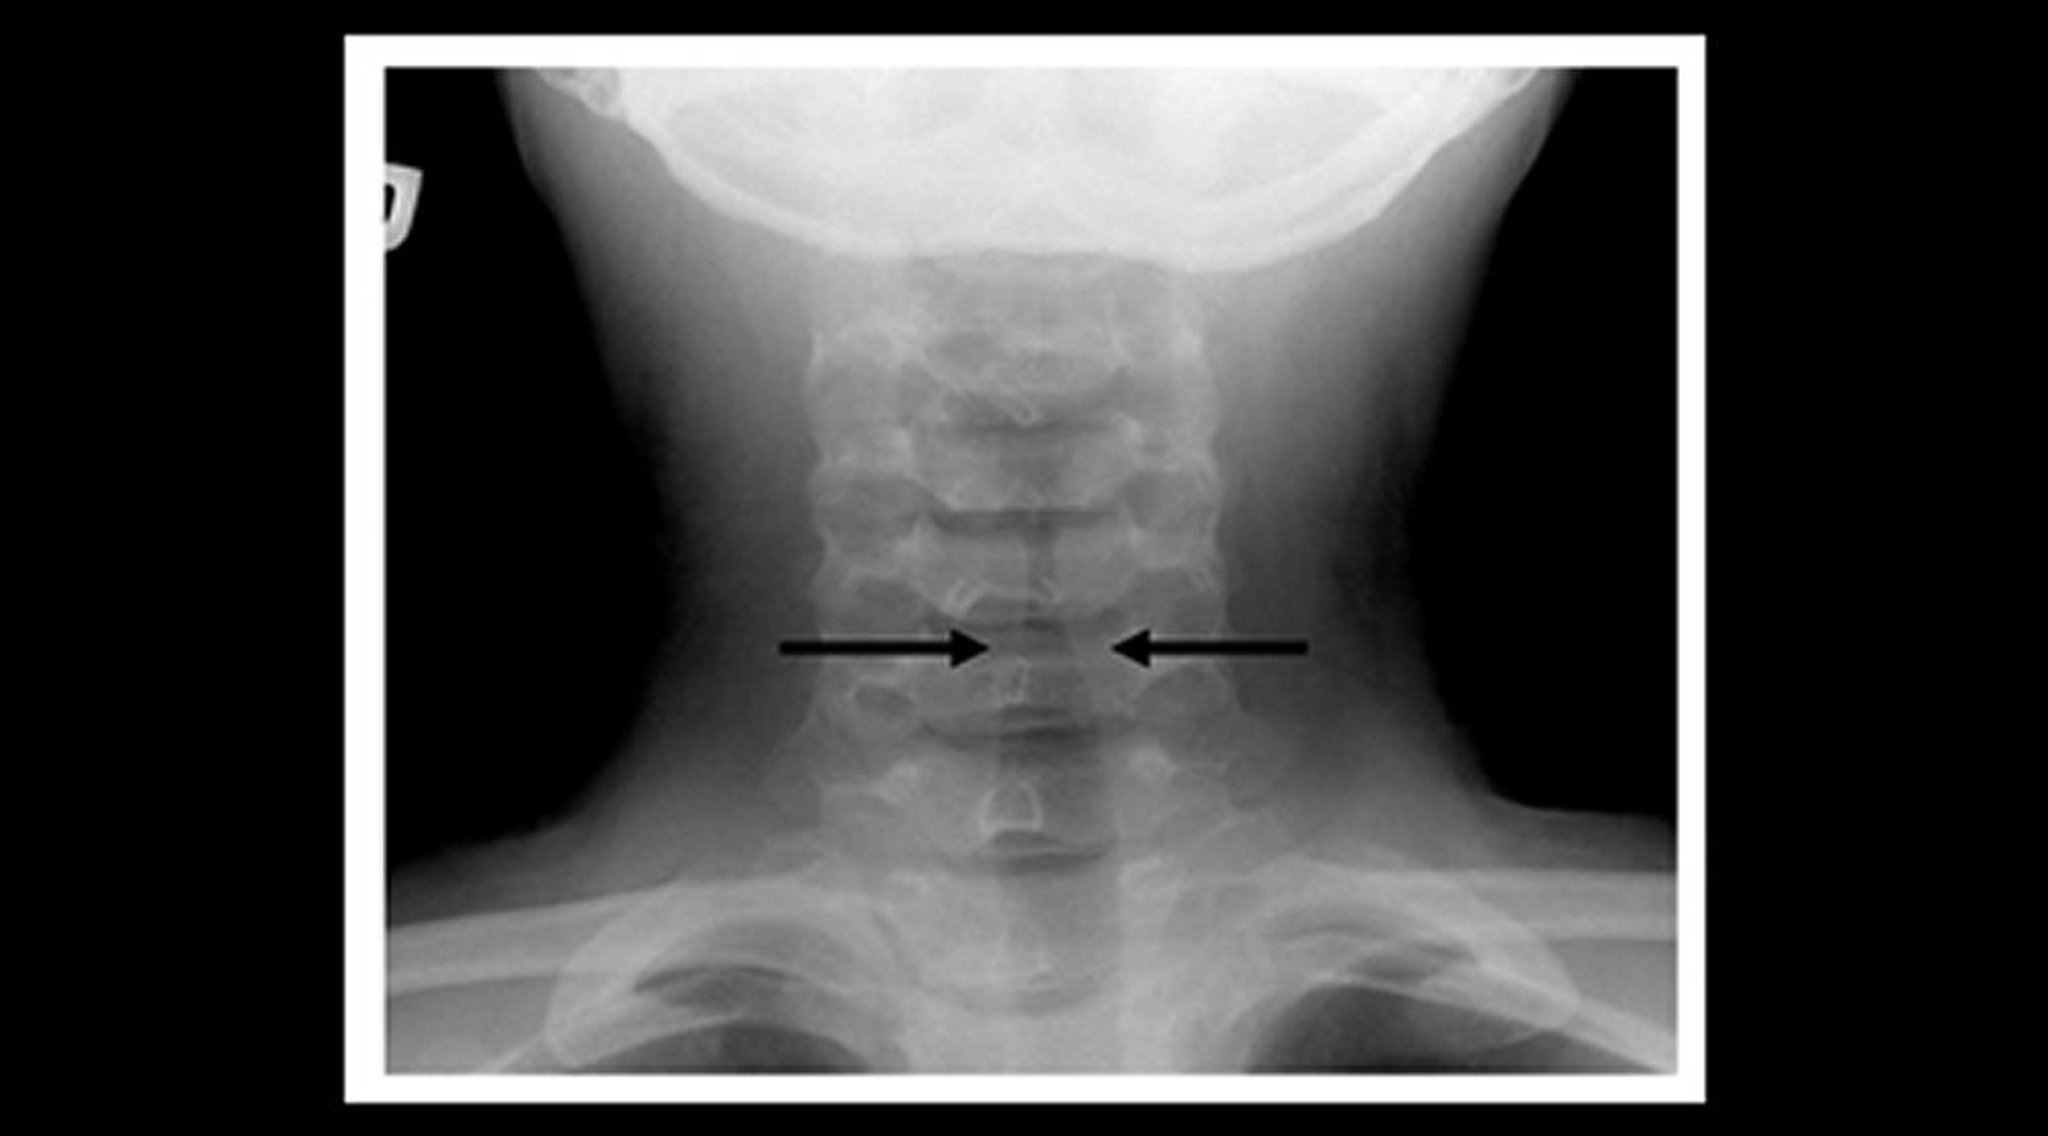

Рентгенография у ребенка с крупом (корональная проекция)

При рентгенологическом исследовании мягких тканей шеи у ребенка с крупом выявлено постепенное сужение эндотрахеальной трубки ниже складок голосовой щели (симптом "шпиля"– обозначен стрелкой) и расширение фарингальных просветов.